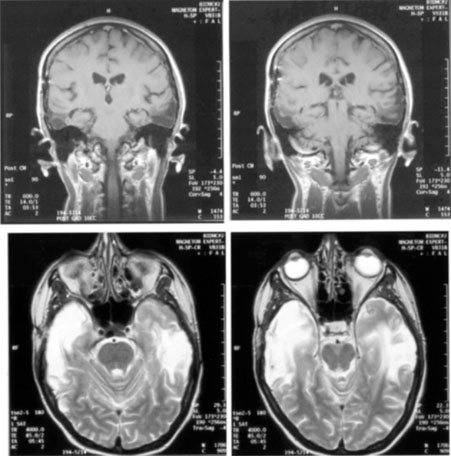

Fig. 15. Bilateral incomplete hemianopia. A 69-year-old man with decreased vision after prostate surgery. A. Fields show remaining central parafoveal vision with some sparing of inferior left quadrant. Note how the defect respects the vertical meridian. B. MRI shows bilateral medial occipital infarction, with sparing of the occipital poles, accounting for the macular-sparing bilaterally. (Courtesy of Dr. Lucia Vaina.)

Bilateral lesions of striate cortex are not rare. Focal midline lesions such as tumors or traumatic injury may affect both striate cortices concurrently, because the right and left striate cortices face each other on the medial occipital surface. The most common cause, however, is posterior circulation ischemia.57 This can affect both striate cortices either simultaneously or sequentially,57 because the right and left posterior cerebral arteries have a common origin from the basilar artery. Twenty-two percent of patients with a unilateral occipital infarction develop bilateral infarction over 3 years.58 Bilateral incomplete hemianopia is distinguished from bilateral optic nerve or ocular disease by the high congruity of the visual fields and step defects along the vertical meridian which indicate the hemifield nature of the visual loss (Fig. 15).57 Such steps are important to seek with a skilled perimetrist, but even so they can be difficult to demonstrate with bilateral hemiscotomata from occipital pole lesions.59 Bilateral quadrantanopias can occur,47,48 often in patients with prosopagnosia and achromatopsia for example, and may mimic the altitudinal defects of optic neuropathy.